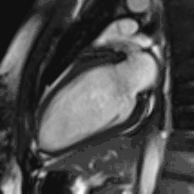

![]() نمونه ای از تصاویر CMRدر جهتهای مختلف تومور قلبی - در این مورد، میگزوم قلبی.[1] | |